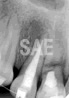

En noviembre de 1996 concurre a la consulta un varón de 19 años de edad que había sufrido un traumatismo frontal 4 meses atrás y no había recibido ningún tipo de tratamiento. El examen clínico reveló que el incisivo central superior derecho estaba extruído y presentaba marcada movilidad. Las pruebas de vitalidad pulpar fueron negativas. El examen radiográfico con diferentes angulaciones reveló la presencia de una fractura horizontal en el tercio medio con tendencia a extenderse hacia cervical, con desplazamiento de los cabos de fractura aunque de ubicación totalmente intraósea, sin relación con el fondo del surco gingival. Se detectaron áreas de reabsorción en el extremo de los cabos entre los que se observó un área radiolúcida (Fig.1). Dado que la pulpa no presentaba signos de vitalidad, que habían transcurrido 4 meses desde que se produjo el traumatismo y los cabos de fractura no pudieron ser reubicados, no se hizo reducción ni contención realizándose si, el tratamiento endodóntico. Luego de aislar convenientemente, se instrumento por tercios, incluyendo el segmento superior e irrigando copiosamente con hipoclorito de sodio al 1 % alternando con clorhexidina al 0,2%. Se utilizó como medicación tópica entre sesiones una pasta constituida por hidróxido de calcio y propilenglicol (Fig.2). El primer control se realizó a los 45 días. Se pudo comprobar una marcada reducción de la movilidad realizándose el recambio de la pasta 45 días después, o sea a 90 días del inicio del tratamiento, se obturó definitivamente el conducto radicular hasta el límite de la fractura. Como su diámetro era excesivamente amplio se utilizó en forma invertida un cono de condensación lateral de tipo D (Maillefer, Ballaigues, Switzerland) realizándose posteriormente la condensación lateral de conos auxiliares (Maillefer) complementados con Endomethasone (Septodont, Cedex, France), como sellador (Fig.3). Se realizaron controles clínicos y radiográficos a los 6 meses y posteriormente cada 12 meses durante 5 años no observándose aumento en la movilidad de la pieza dentaria fracturada. Radiográficamente se detectó el desarrollo progresivo de un tejido calcificado interpuesto entre los cabos de fractura (Figs.4 y 5).

Fig. 1: Fractura radicular en el tercio medio del inc. sup. dere. con desplaz. de los cabos de fractura y reabs |